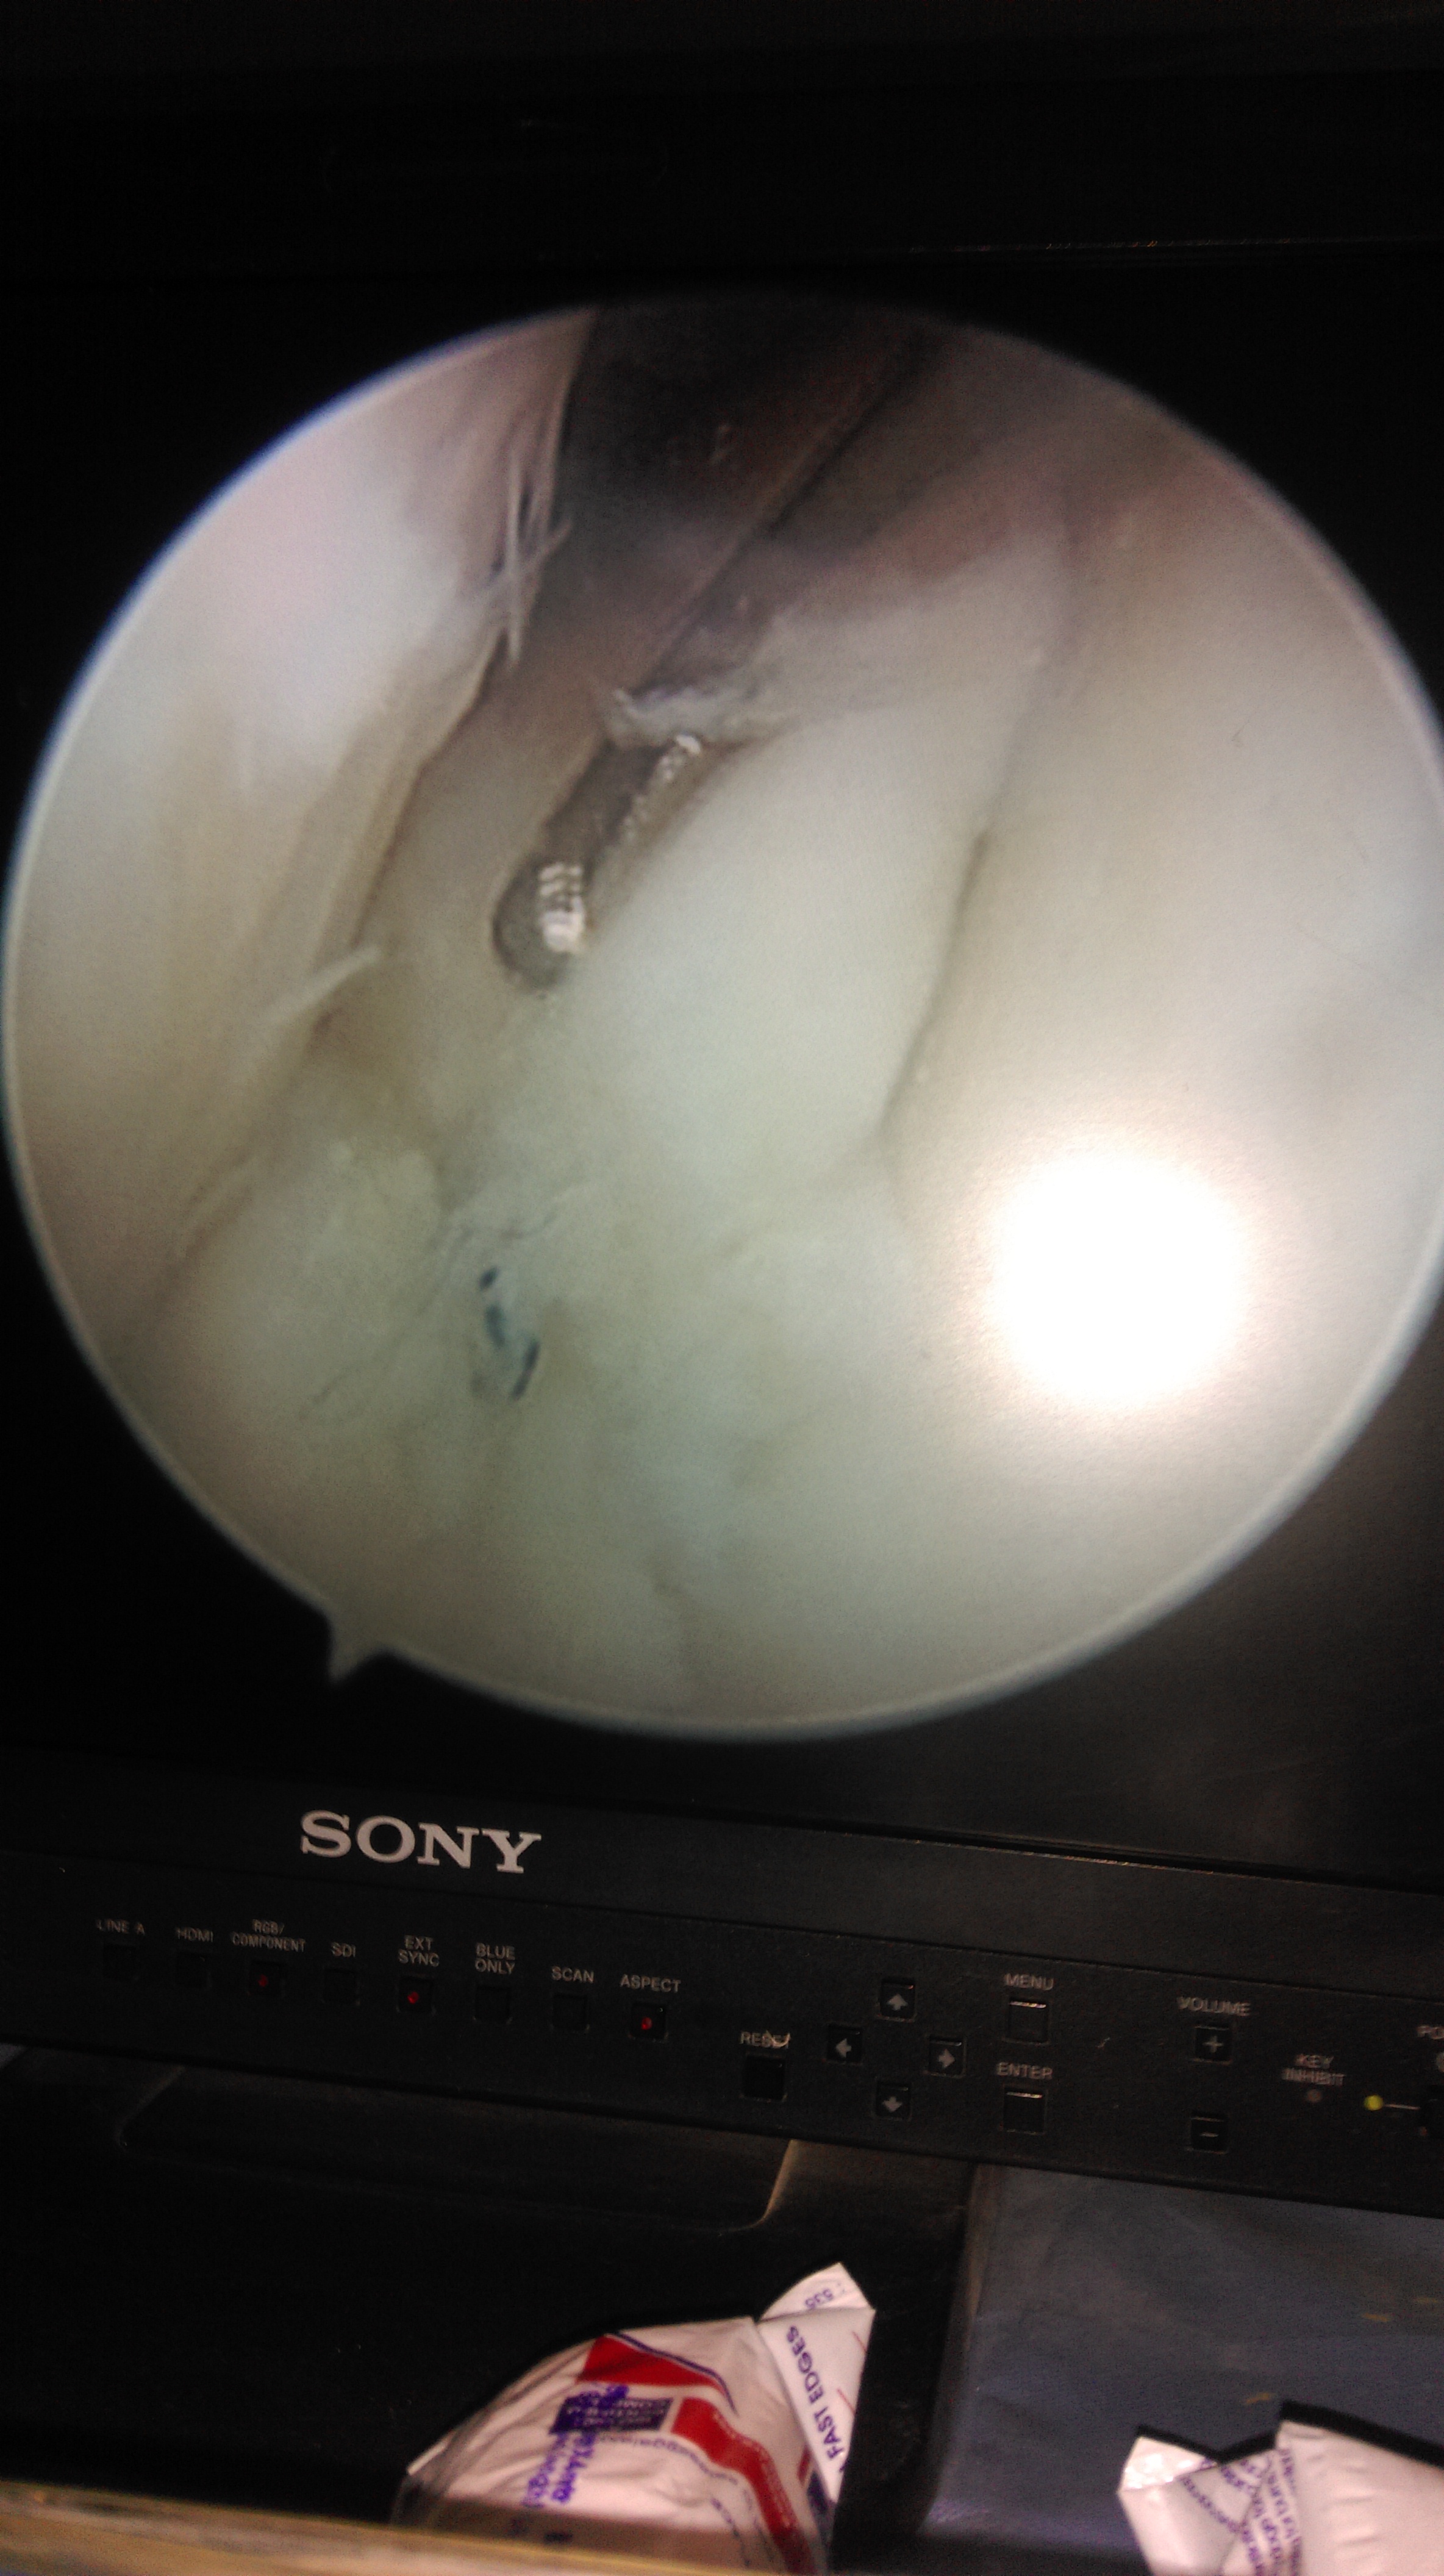

Orthopaedic surgeons perform arthroscopic surgery by making a small incision in the patient’s skin and inserting pencil-size instruments that contain a small lens and lighting system to magnify and illuminate the structures inside the joint. A fibre optic cable transmits light to the end of the arthroscope inserted into the joint. An arthroscope is attached to a miniature camera so the surgeon can see inside the joint through this small incision rather than a larger one required for open surgery.

A small incision (about the size of a buttonhole) will be made to insert the arthroscope. Several other incisions may be made to see other parts of the joint or insert other instruments.

Corrective surgery is performed with specially designed instruments that are inserted into the joint through accessory incisions. Originally, arthroscopy was simply a diagnostic tool used for planning standard open surgery.